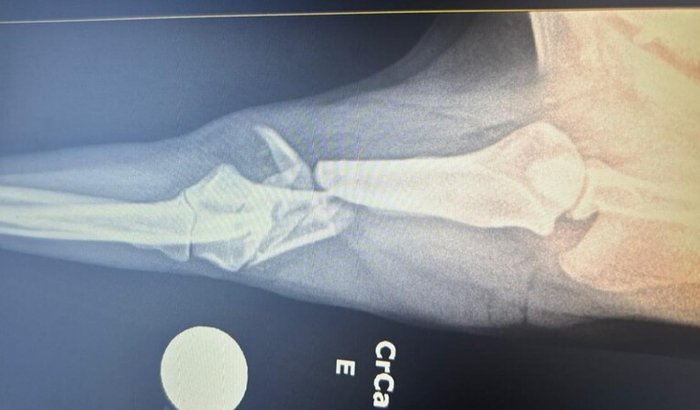

Minha cachorra foi atropelada e quebrou a pata. A única chance de recuperação é uma cirurgia urgente no valor de R$ 2.000,00. No momento, não consigo pagar sozinha, por isso criei essa vaquinha para tentar salvar a pata dela.